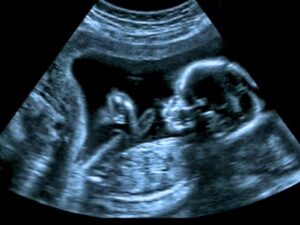

En el marco del Día Mundial de la Eliminación de las Sífilis Congénita, la Secretaría de Salud Jalisco (SSJ), a través del Consejo Estatal para la Prevención del SIDA en Jalisco (COESIDA), hace un llamado a la población, especialmente a mujeres embarazadas y sus parejas a realizarse la prueba de sífilis durante el primer y tercer trimestre del embarazo.

La sífilis es una infección bacteriana causada por Treponema pallidum, que puede transmitirse por contacto sexual o de la persona gestante al bebé durante el embarazo o el parto (sífilis congénita).

En los recién nacidos, puede ocasionar afectaciones en diversos órganos y sistemas, como el sistema nervioso central, los huesos, la piel y las mucosas, así como en el hígado, los ojos y los oídos, incluso de manera tardía.

Al respecto, una publicación de los National Institutes of Health (NIH), revela que la sífilis congénita se debe a la transmisión de la espiroqueta Treponema pallidum de la madre al feto, lo que da lugar a diversas presentaciones clínicas:

“La sífilis congénita en un feto a veces se asocia con un bebé a término aparentemente sano, pero también puede causar prematuridad o muerte fetal”.